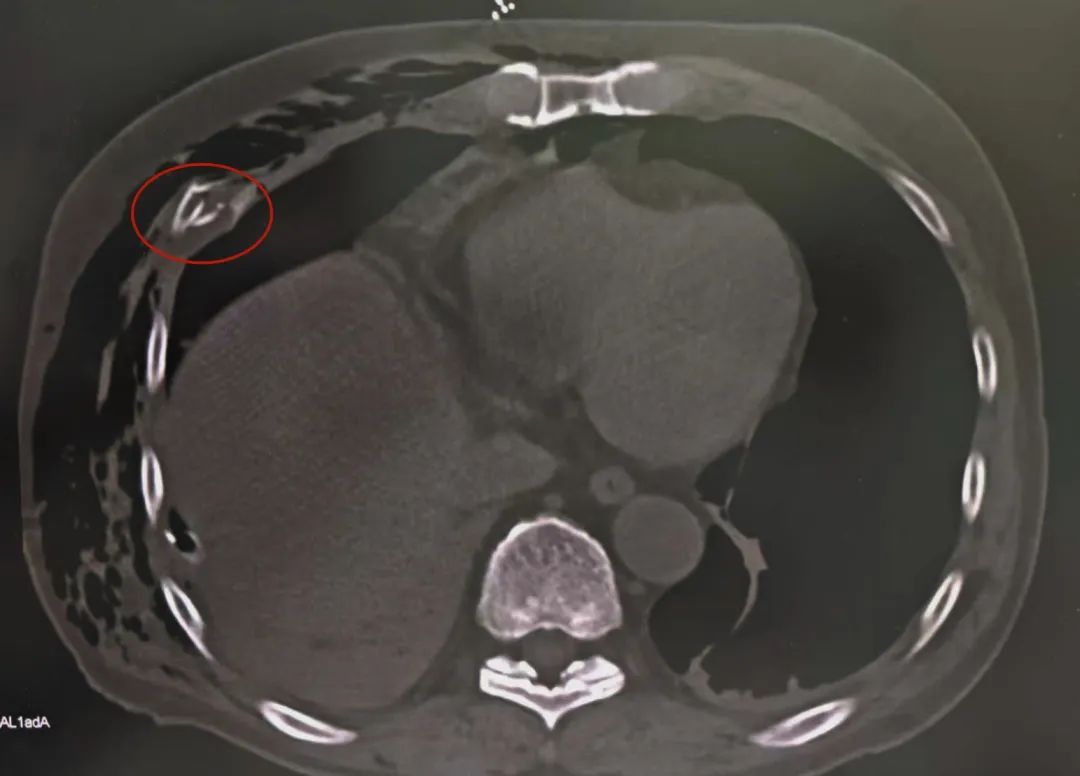

多处骨折

系统检查提示:罗叔目前存在车祸后多发伤,头部、胸部、腹部等存在多处外伤,颅脑的挫裂伤,右侧颌面部撕裂伤,右肘关节皮肤裂伤等全身多处皮肤擦伤。外表的伤口已经足够狰狞,而在罗叔的身体内部存在更严重的情况:闭合性颅脑损伤、呼吸衰竭、右侧6根肋骨骨折伴血气胸和皮下气肿、代谢性酸中毒、呼吸性碱中毒,还有肝、肺挫伤等脏器损伤。